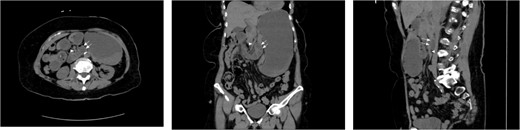

An 80-year-old female presented with symptoms of bowel obstruction. Her medical history was significant for hypertension, diabetes, and a total abdominal hysterectomy through a Pfannenstiel. She presented with ~1 day of colicky abdominal pain, nausea, vomiting, and denied previous episodes of similar symptoms. Physical exam revealed a soft but diffusely tender abdomen without peritoneal signs. Laboratory evaluation was significant for white blood cell count of 15 400 and a lactate of 3.6. A computed tomography (CT) scan of the abdomen was performed, which demonstrated a markedly dilated stomach and proximal small bowel, which was not the duodenum, in a retroperitoneal position. Images of the admission CT scan are depicted below (Fig. 3). Based on the concern for a paraduodenal hernia raised by imaging, as well as elevated white count and lactate, she was taken to the operating room for diagnostic laparoscopy which revealed that a majority of the jejunum was incarcerated within a left paraduodenal hernia. The bowel was reduced by gentle traction and found to be viable. The patient demonstrated evidence of chronic small bowel obstructions with several pulsion-type diverticula present due to recurrent episodes of occult obstruction. The mouth of the hernia defect, identified as Landzert’s fossa based upon its position at the base of the transverse mesocolon and nested between the proximal jejunum and the IMV, was closed with nonabsorbable suture. The operation was completed entirely laparoscopically with the patient experiencing no complications.

CT cross sectional images of Case 1, axial, coronal, and sagittal, respectively. Note the position of the dilated afferent small bowel (double arrow) posterior to the SMA (single arrowhead), thus confirming the retroperitoneal position of the entrapped bowel. Also note that while left paraduodenal hernias are typically described as existing in the left retroperitoneal position, there is no fixed midline barrier preventing their herniation to the across right of midline. In either case, the peritoneal defect, Landzert’s fossa, is the same with identical surrounding landmarks.